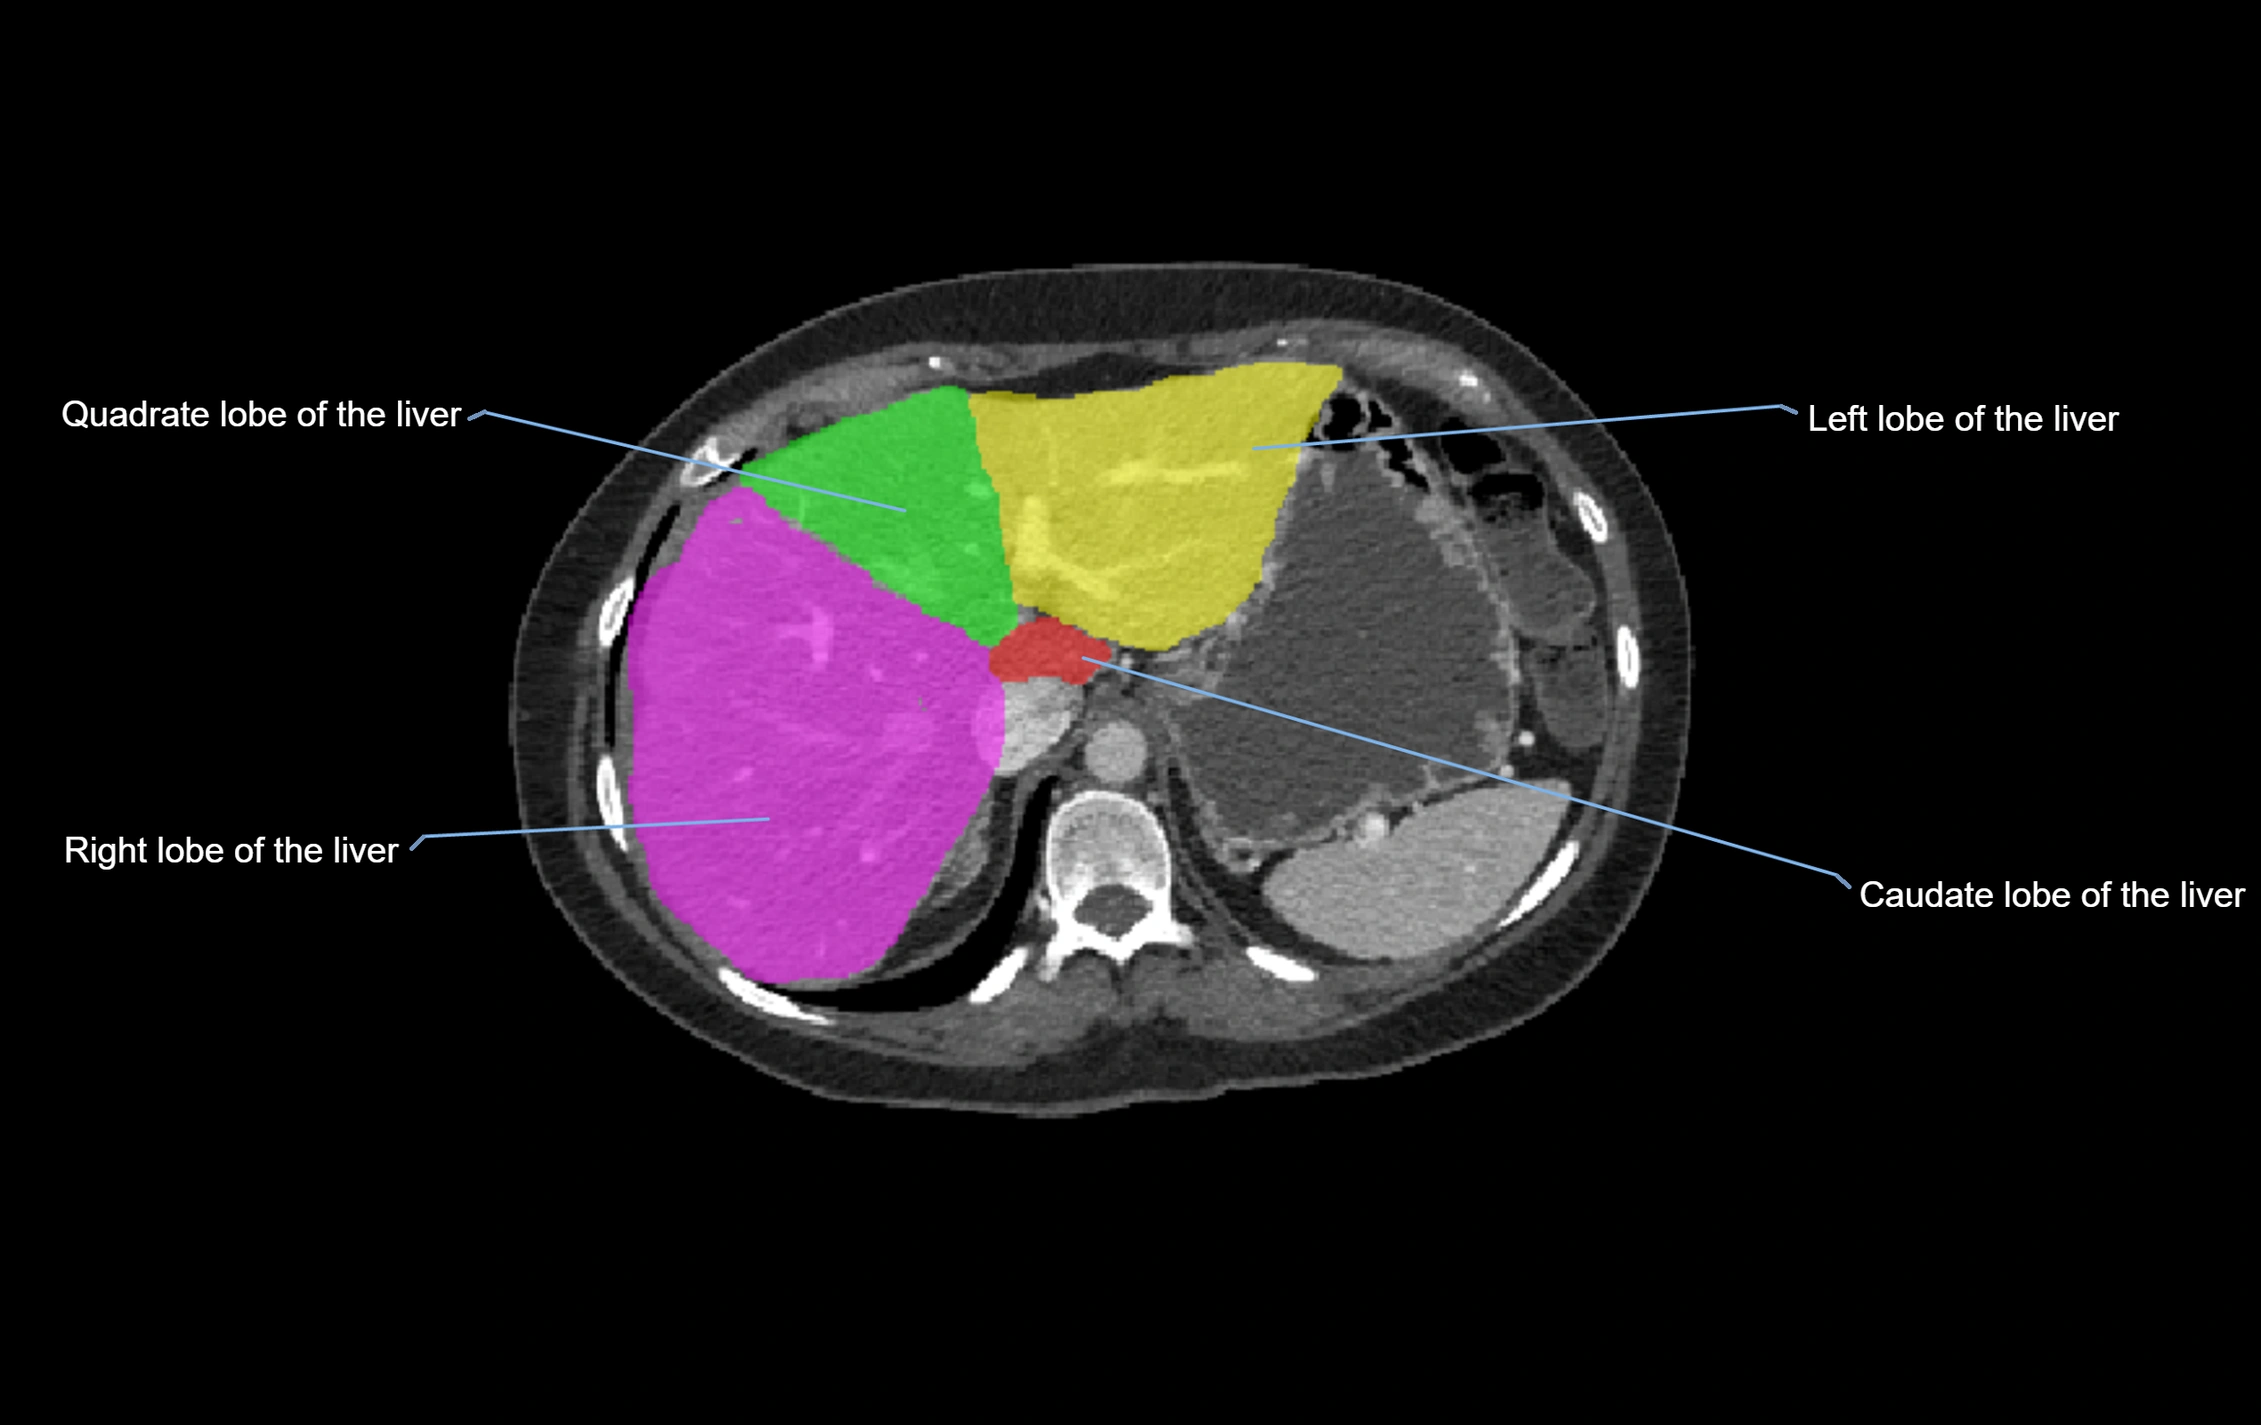

The caudate lobe of the liver is a distinct anatomical subdivision of the liver, designated as segment I in Couinaud’s classification. It lies on the posterior surface of the liver, between the fissure for the ligamentum venosum (left boundary) and the groove for the inferior vena cava (IVC) (right boundary). Superiorly, it is related to the posterior liver surface, and inferiorly it is separated from the left lobe by the porta hepatis.

image

CT Image